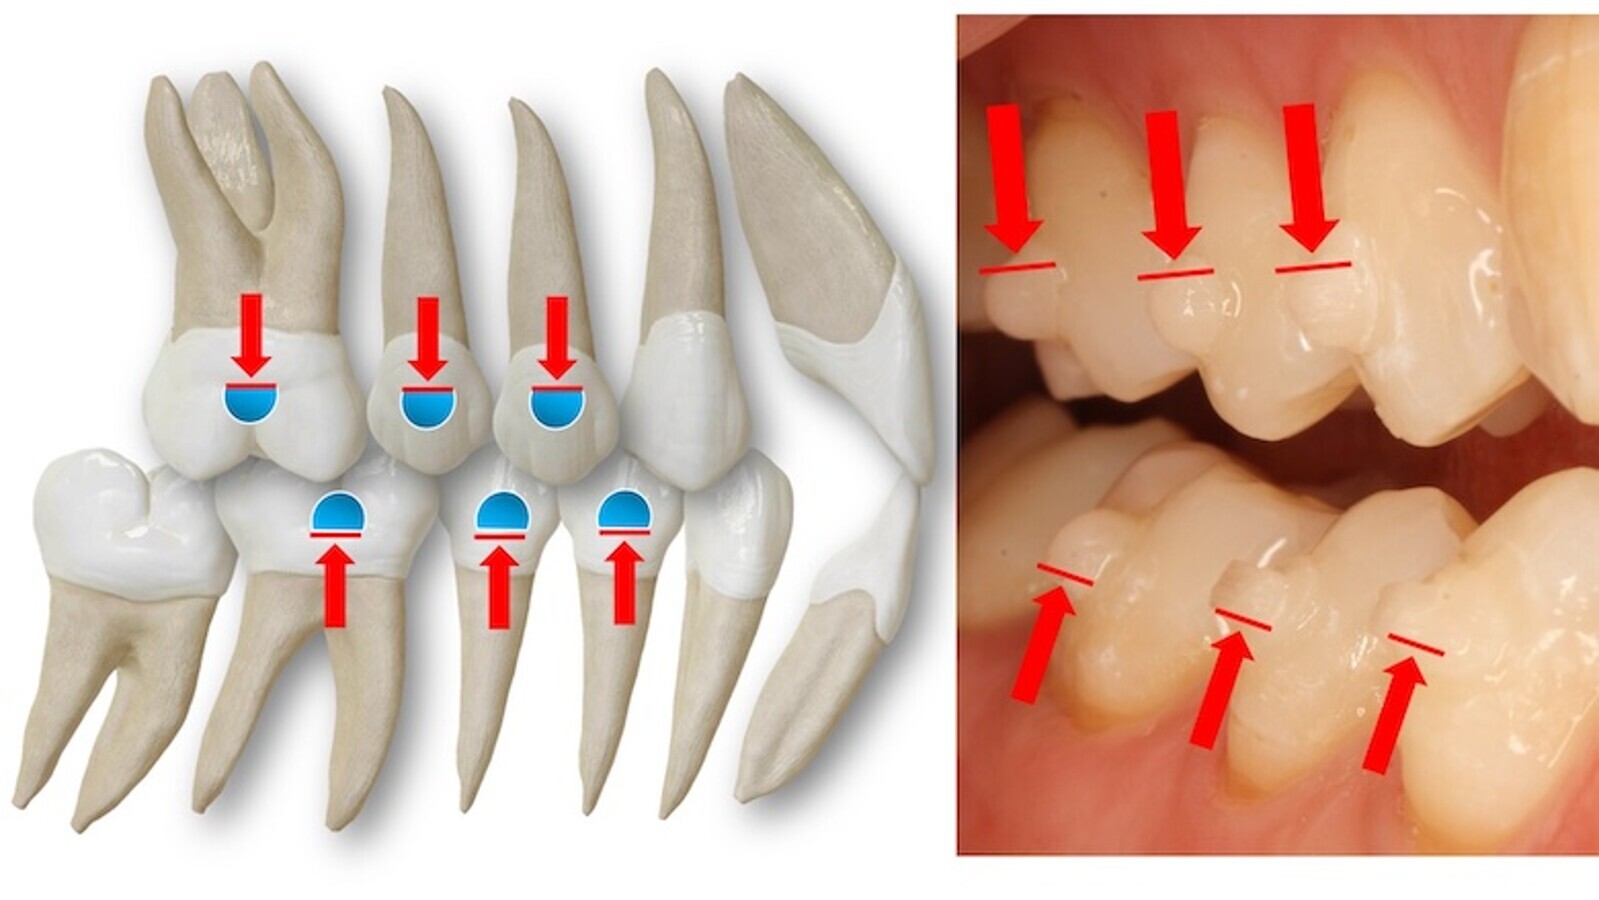

El movimiento de intrusión es otro ejemplo muy válido para comprender las diferencias biomecánicas entre utilizar brackets vestibulares, brackets linguales o alineadores (figura 2).

Figura 2. El movimiento de intrusión es un ejemplo de las diferencias biomecánicas entre utilizar brackets vestibulares, brackets linguales o alineadores.

La fuerza de intrusión que produce el arco en los brackets vestibulares pasa alejada del centro de resistencia del diente y esto genera un momento o inclinación vestibular del diente simultáneo al movimiento de intrusión. Si queremos evitar este momento o disminuirlo podemos actuar de dos maneras: dando torsión al diente con un arco rectangular que rellene la ranura o slot (par de fuerzas para generar torsión radicular negativa) o cinchando en distal el arco (control de la longitud de arcada). Cuando el bracket lo colocamos en lingual, su posición es cercana al eje mayor del diente y la fuerza de intrusión del arco pasa muy cerca del centro de resistencia radicular, disminuyendo el momento. Algo similar ocurre con los alineadores cuando añadimos en el plástico un punto de presión (PP) que redirija y concentre la fuerza de intrusión del plástico en la cara palatina del incisivo. Por tanto, la biomecánica a aplicar en uno u otro caso dependerá de nuestro plan de tratamiento y la necesidad, o no, de acompañar a nuestro movimiento de intrusión de un componente de inclinación vestibular. Debemos de realizar un movimiento combinado intrusión-inclinación en los típicos incisivos centrales lingualizados de la maloclusión de Clase II división 2ª y será más pura la intrusión, con mayor control de la torsión, en los centrales de la Clase II división 1º o en incisivos con una adecuada inclinación previa a la intrusión (figura 2).